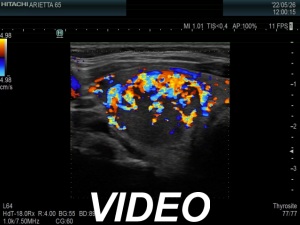

Ultrasonography. The thyroid was echonormal. There was a moderately hypoechoic nodule in the right lobe. The nodule has halo and presents with a combined perinodular and intranodular blood flow. The latter was irregularly increased.

The presentation of the nodule is not very suspicious. Halo sign is a rare finding in medullary cancers.

The classification of the nodule depends on the judgement of nodule borders. If it is regarded as irregular, then the lesion is an EU-TIRADS 5 one. However, if we judge the borders as non-lobulated, then the lesion is an EU-TIRADS 4 nodule. According to the EU-TIRADS, FNA is indicated in both cases because the largest diameter of the nodule exceeds 15 mm.